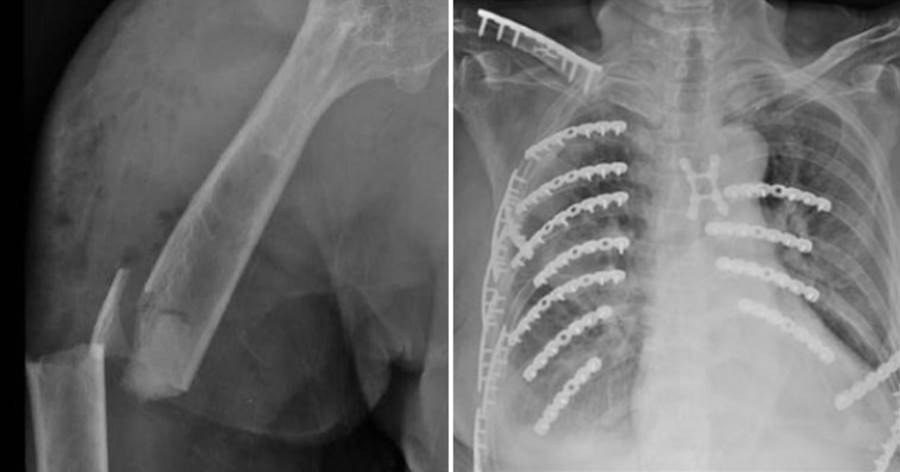

黃婦事發當天做完太空包的工作後,騎機車返家途中,遭一輛小貨車撞上,緊急被送往彰化醫院急診,全身都是傷,右上臂開放性骨折、右側血胸,右鎖骨、肱骨、橈骨、第3至5掌骨、骨盆、脛骨、腓骨,及第6至9節胸椎、胸骨、2側多處肋骨皆出現骨折。

胸腔外科主任林聿騰表示,黃婦光肋骨就斷了21處,血胸、氣胸及胸廓變形,造成嚴重錯位的「連枷胸」,也就是相鄰3根以上的肋骨骨折,恐引發肺炎、呼吸衰竭等併發癥,準備開胸手術時,出現延遲性小腸破裂,指的是小腸並未在第一時間破裂,只得緊急穩住病人呼吸,請外科醫師先進行小腸部分切除手術,再進行胸腔手術。

林聿騰指出,整個變形的胸腔透過3D胸廓重組影像定位後進行微創手術,以鈦合金骨板及骨釘進行肋骨固定,穩定整個胸腔,讓患者可以正常呼吸,再交由骨科手術。

骨科醫師陳柏辰提到,黃婦破碎的骨頭如同散落的拼圖,團隊們一次次在手術台上,細心地將每一塊骨頭拼回原位並固定。令人動容的是,黃婦一直很堅毅,即使在加護病房仍保持清醒,咬著呼吸管、全身動彈不得,卻依然努力睜開眼睛,用堅定的目光向他致意。「那雙眼睛裡,充滿了鬥志與希望。她沒有一句抱怨,只有想活下去的力量。」